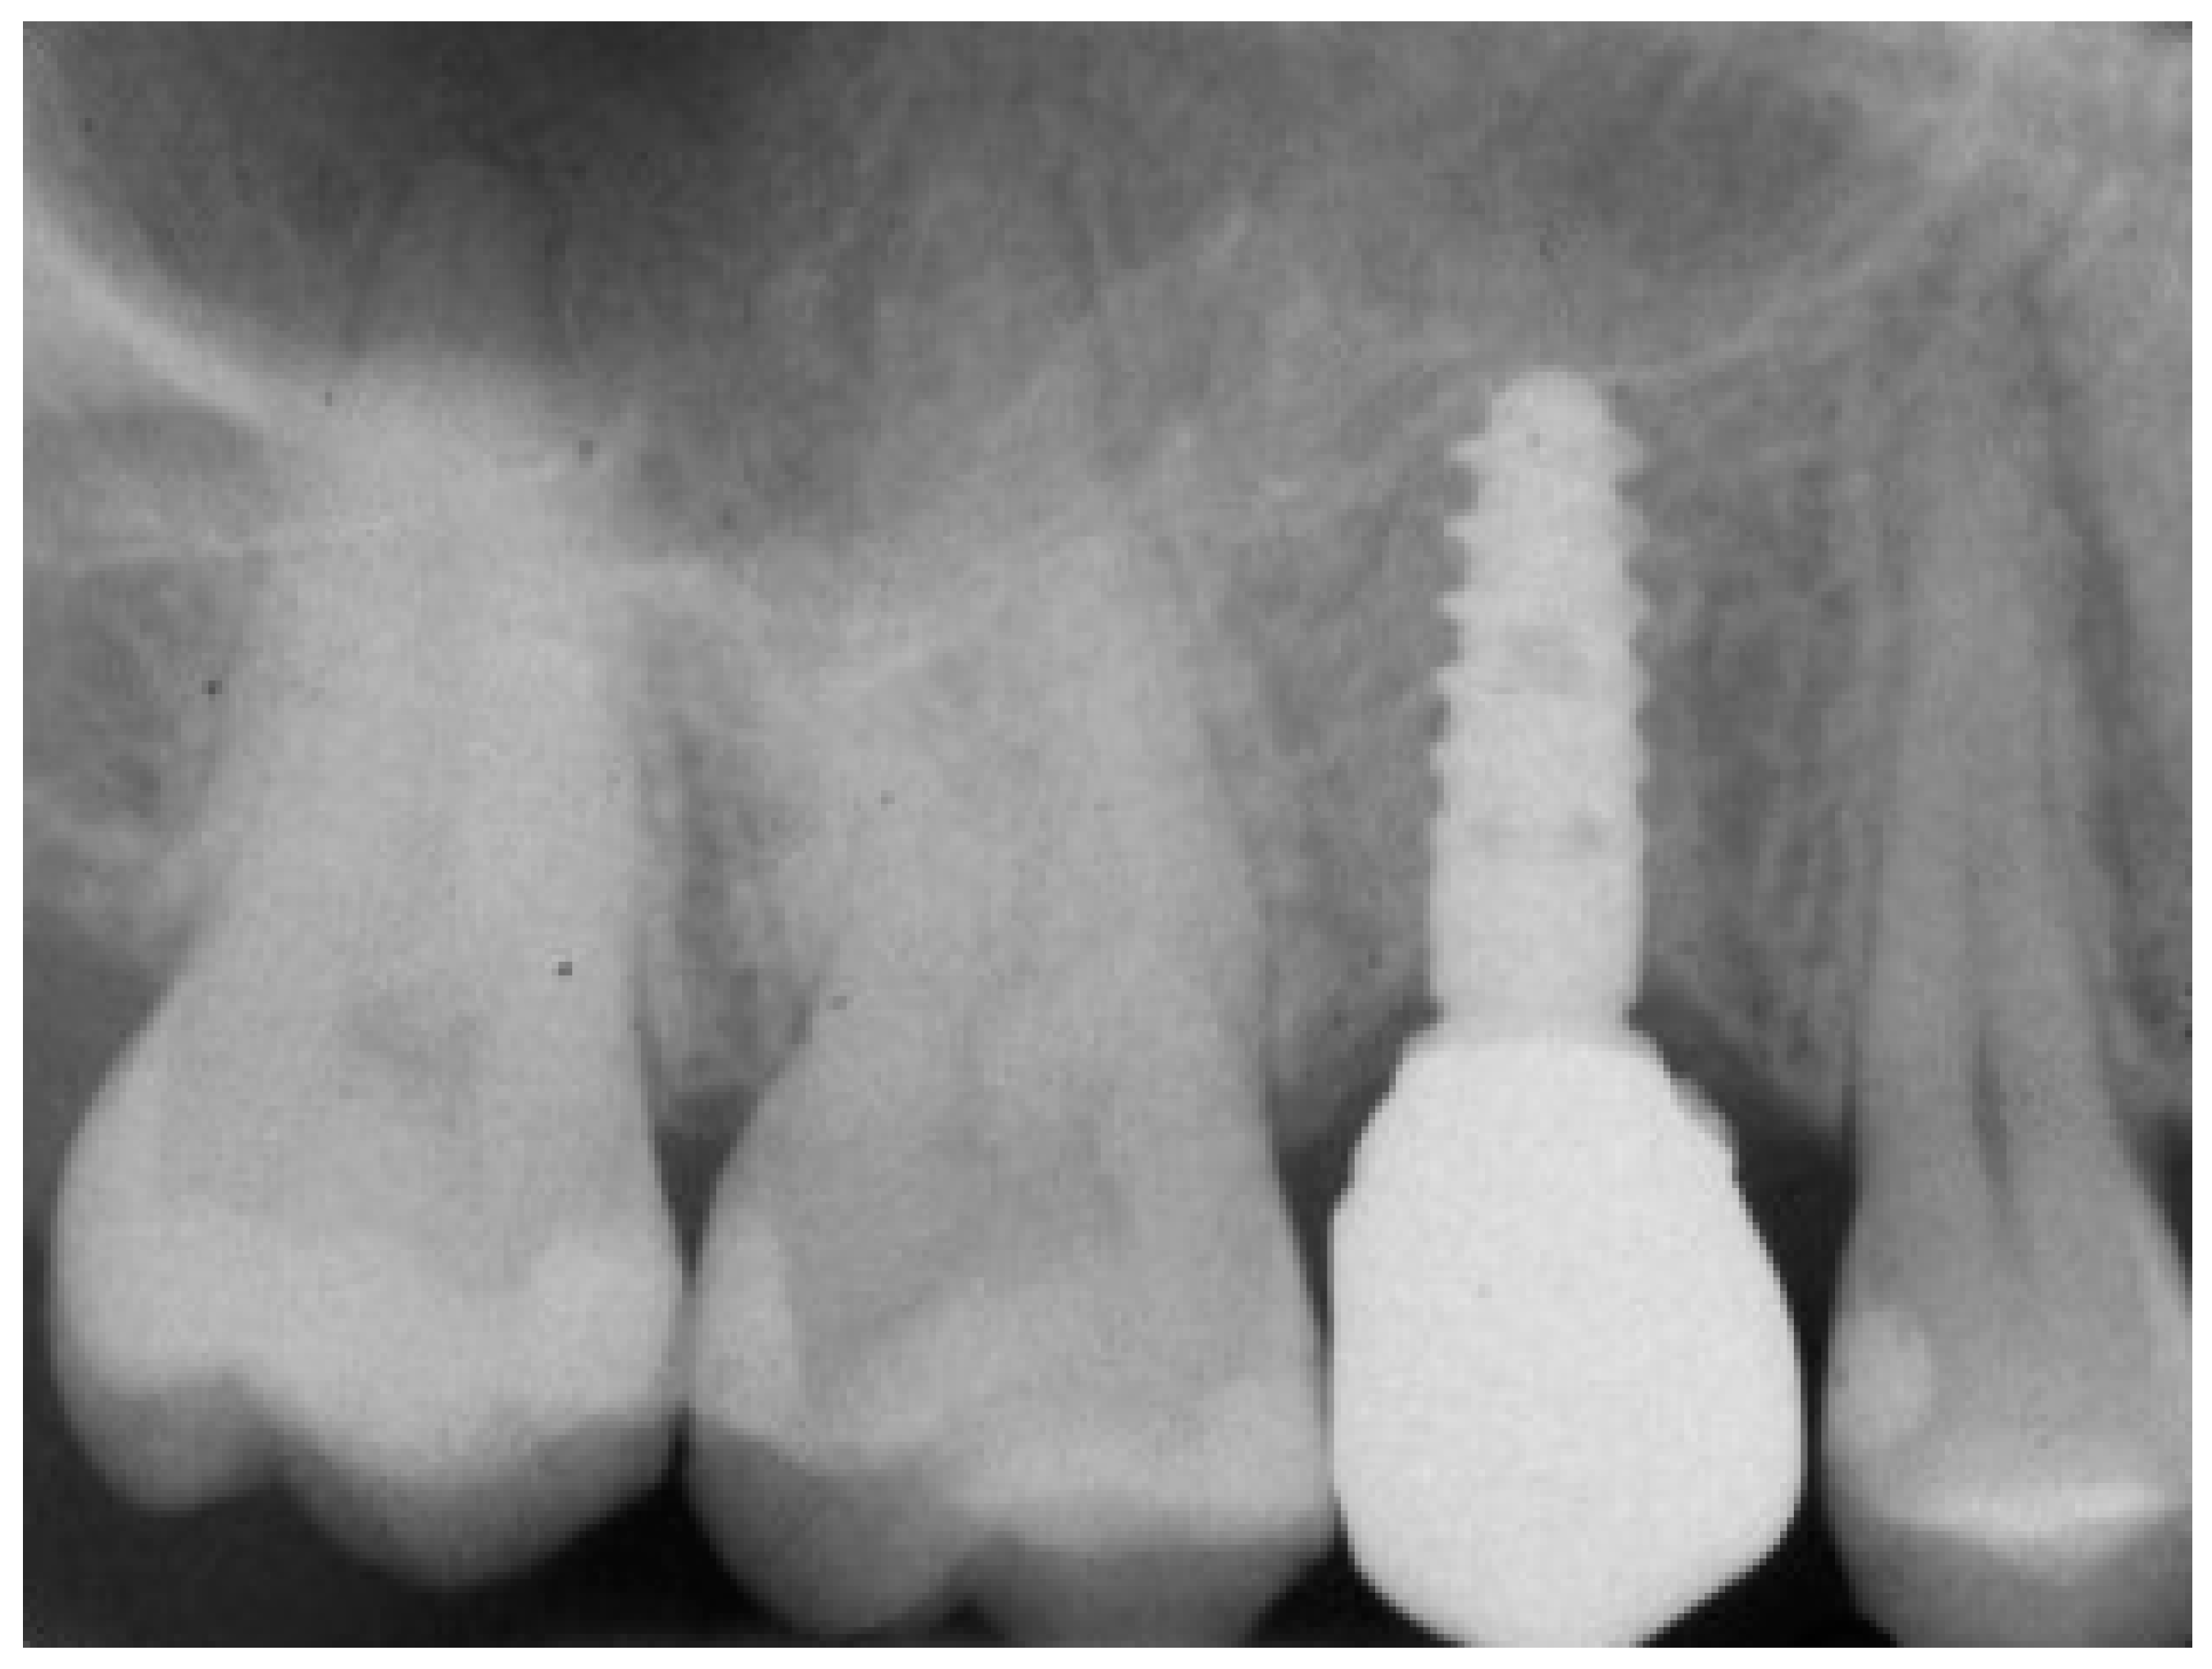

At 1 year year after placement, all 36 implants were regularly functioning, for a survival rate of 100% (36/36 implants surviving) (Figure 15).

Figure 15.

One-year follow-up rx control of the implant supported crown.